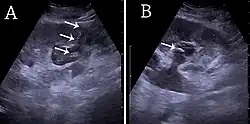

Under normal conditions, the ureter is not seen with US. However, in, e.g., urinary obstruction and vesicoureteric reflux with dilation of the ureter, the proximal part in continuation with the renal pelvis, as well as the distal part near the ostium can be evaluated (Figure 14).[1]

Figure 21. Left hydroureter with ureteric jet. No stone is visible. The red color in the color box represents motion towards the transducer as defined by the color bar.[1]